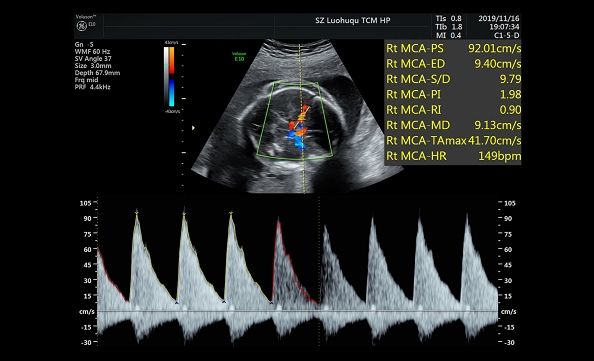

11月19日,第一次胎儿宫内输血手术开始了,熊奕院长、杨艳东教授和周芸主任带领着母胎医学团队有条不紊的进行着输血前的评估:胎儿的情况非常危险,胎儿大脑中动脉峰值血流速度达到92cm/s,胎儿血红蛋白浓度只有37g/L(正常胎儿在150 g/L以上),大家惊叹于如此严重贫血的宝宝的惊人的生命力的同时,也清楚的认识到手术的巨大风险:这个宝宝的心脏功能非常差,输血的过程中随时可能心跳停止。

输血前胎儿MCA PSV 92 cm/s